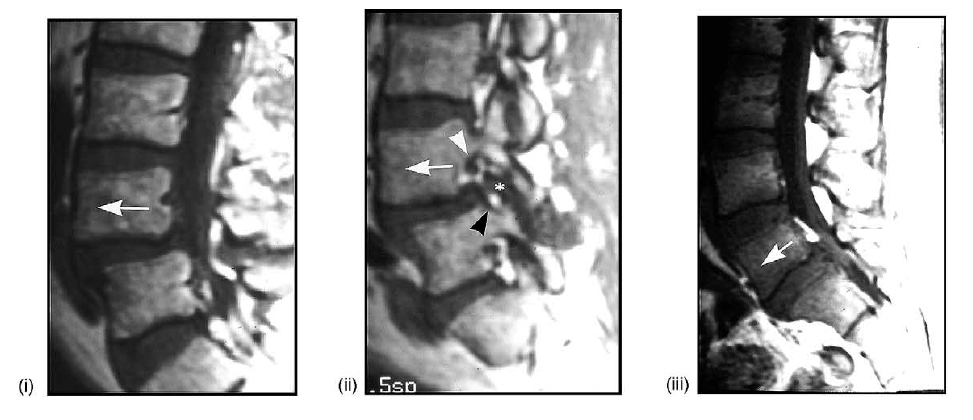

(J) Medical imaging studies:

(i) parasagittal T1-weighted MRI showing collapse of the L5-S1 disk (asterisk) and superoinferior narrowing of the spinal neural foramen (arrow: compare with (A)).

(ii) Parasagittal T2-weighted fat-suppressed MRI showing the posterior spinal facet (zygapophyseal) joint effusion (arrows: compare with (A)).

(iii) Parasagittal CT reconstruction showing the collision of the superior facet process (asterisk) with the overlying pars interarticularis-pedicle junction (dot), and the minor associated osteophytosis (arrow)

(vii) Parasagittal CT reconstruction showing curved remodeling of the superior articular facet process (arrow) of L4-L5 (compare

with (C) and the straight, pointed configuration of the level below: arrowhead).

(viii) Parasagittal T1-weighted MRI showing another case of curved remodeling of the superior articular facet process (arrows; compare with (C)).

(ix) Parasagittal T2-weighted, fat-suppressed MRI showing an anteriorly directed periarticular neocyst (arrow: i.e., synovial cyst) extending into the spinal neural foramen (compare with (D)).